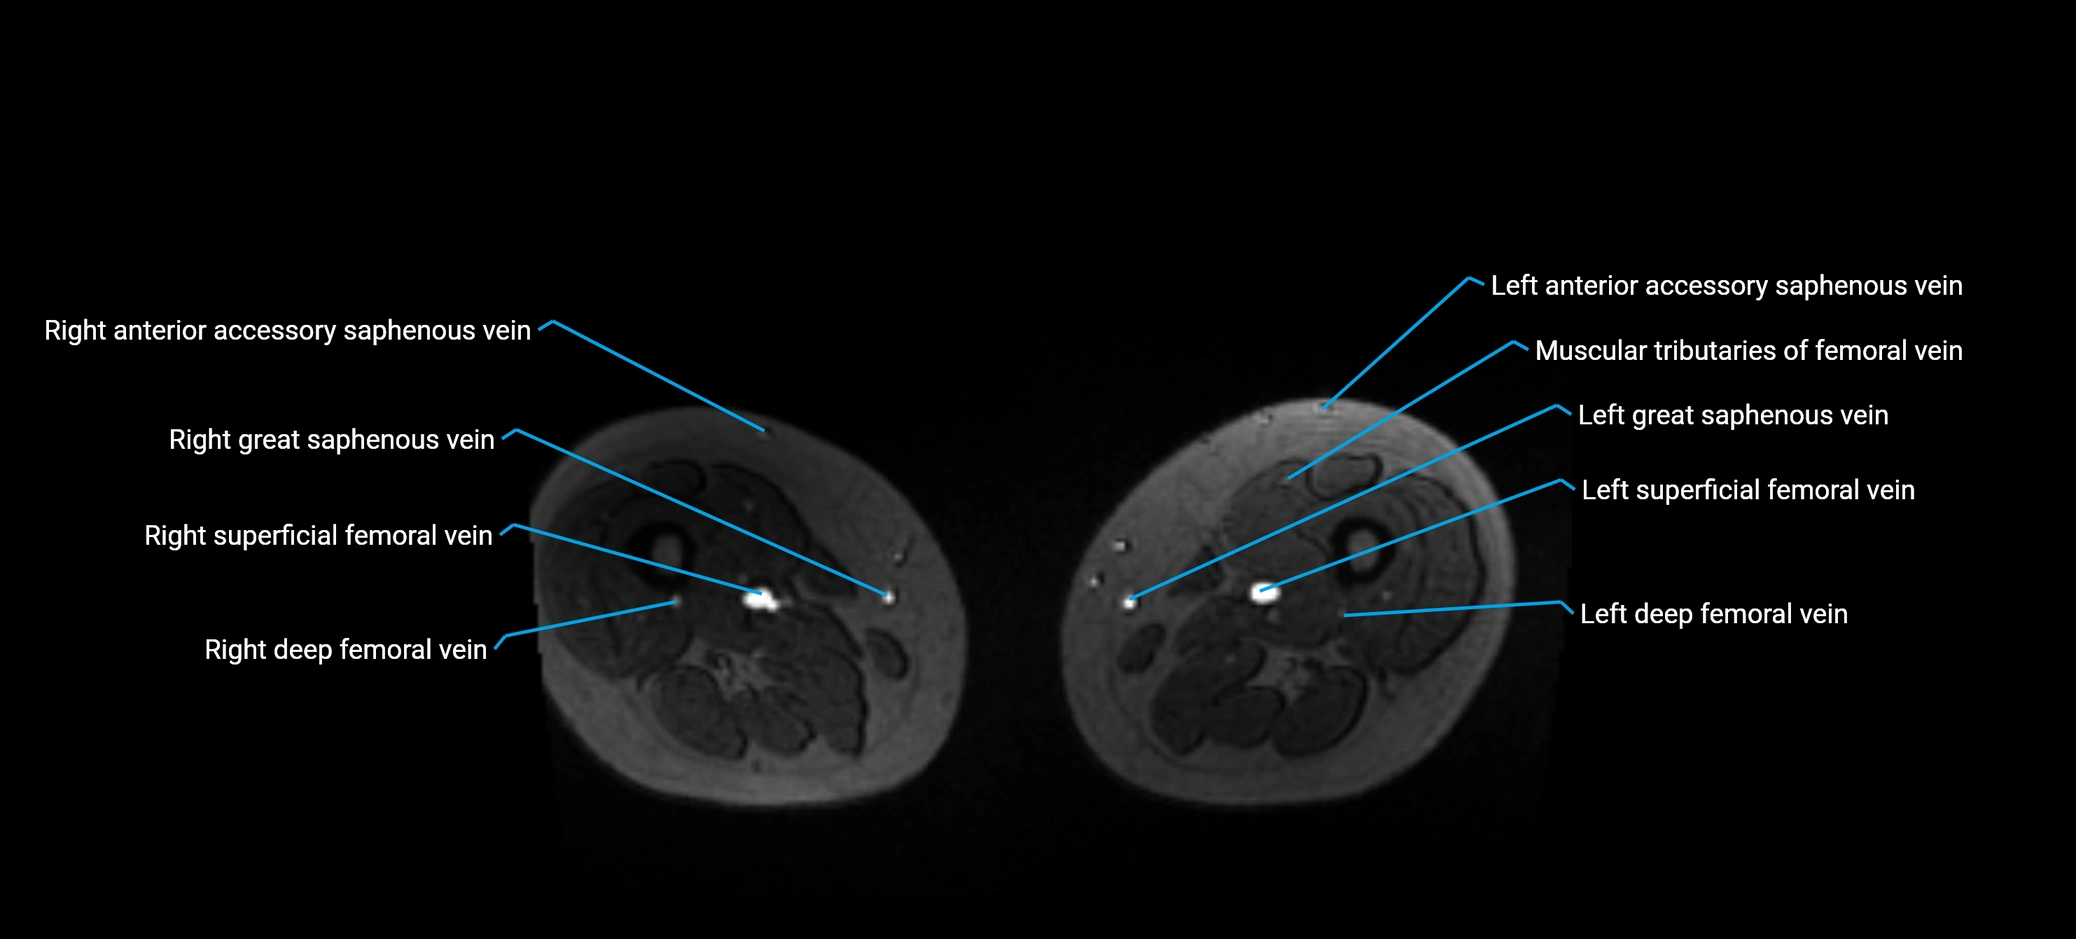

MRI image

image